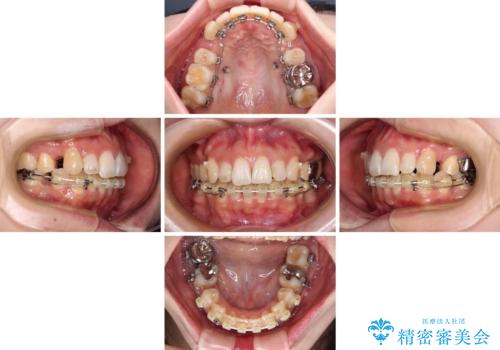

非抜歯矯正にて治療を行うと、仕上がりで口元が突出する可能性があったため、小臼歯抜歯での矯正治療を行うこととしました。

上顎は左右の第一小臼歯2本を、下顎は左右の第二小臼歯2本を抜歯して、口元が突出しないようにしながら、奥歯の咬み合わせを改善していく治療計画としました。

目立たない装置が希望であったため、上顎が裏側装置である、ハーフリンガル装置を選択されました。

第二小臼歯抜歯としたため、治療期間は長くなりましたが、満足のいく仕上がりとなりました。